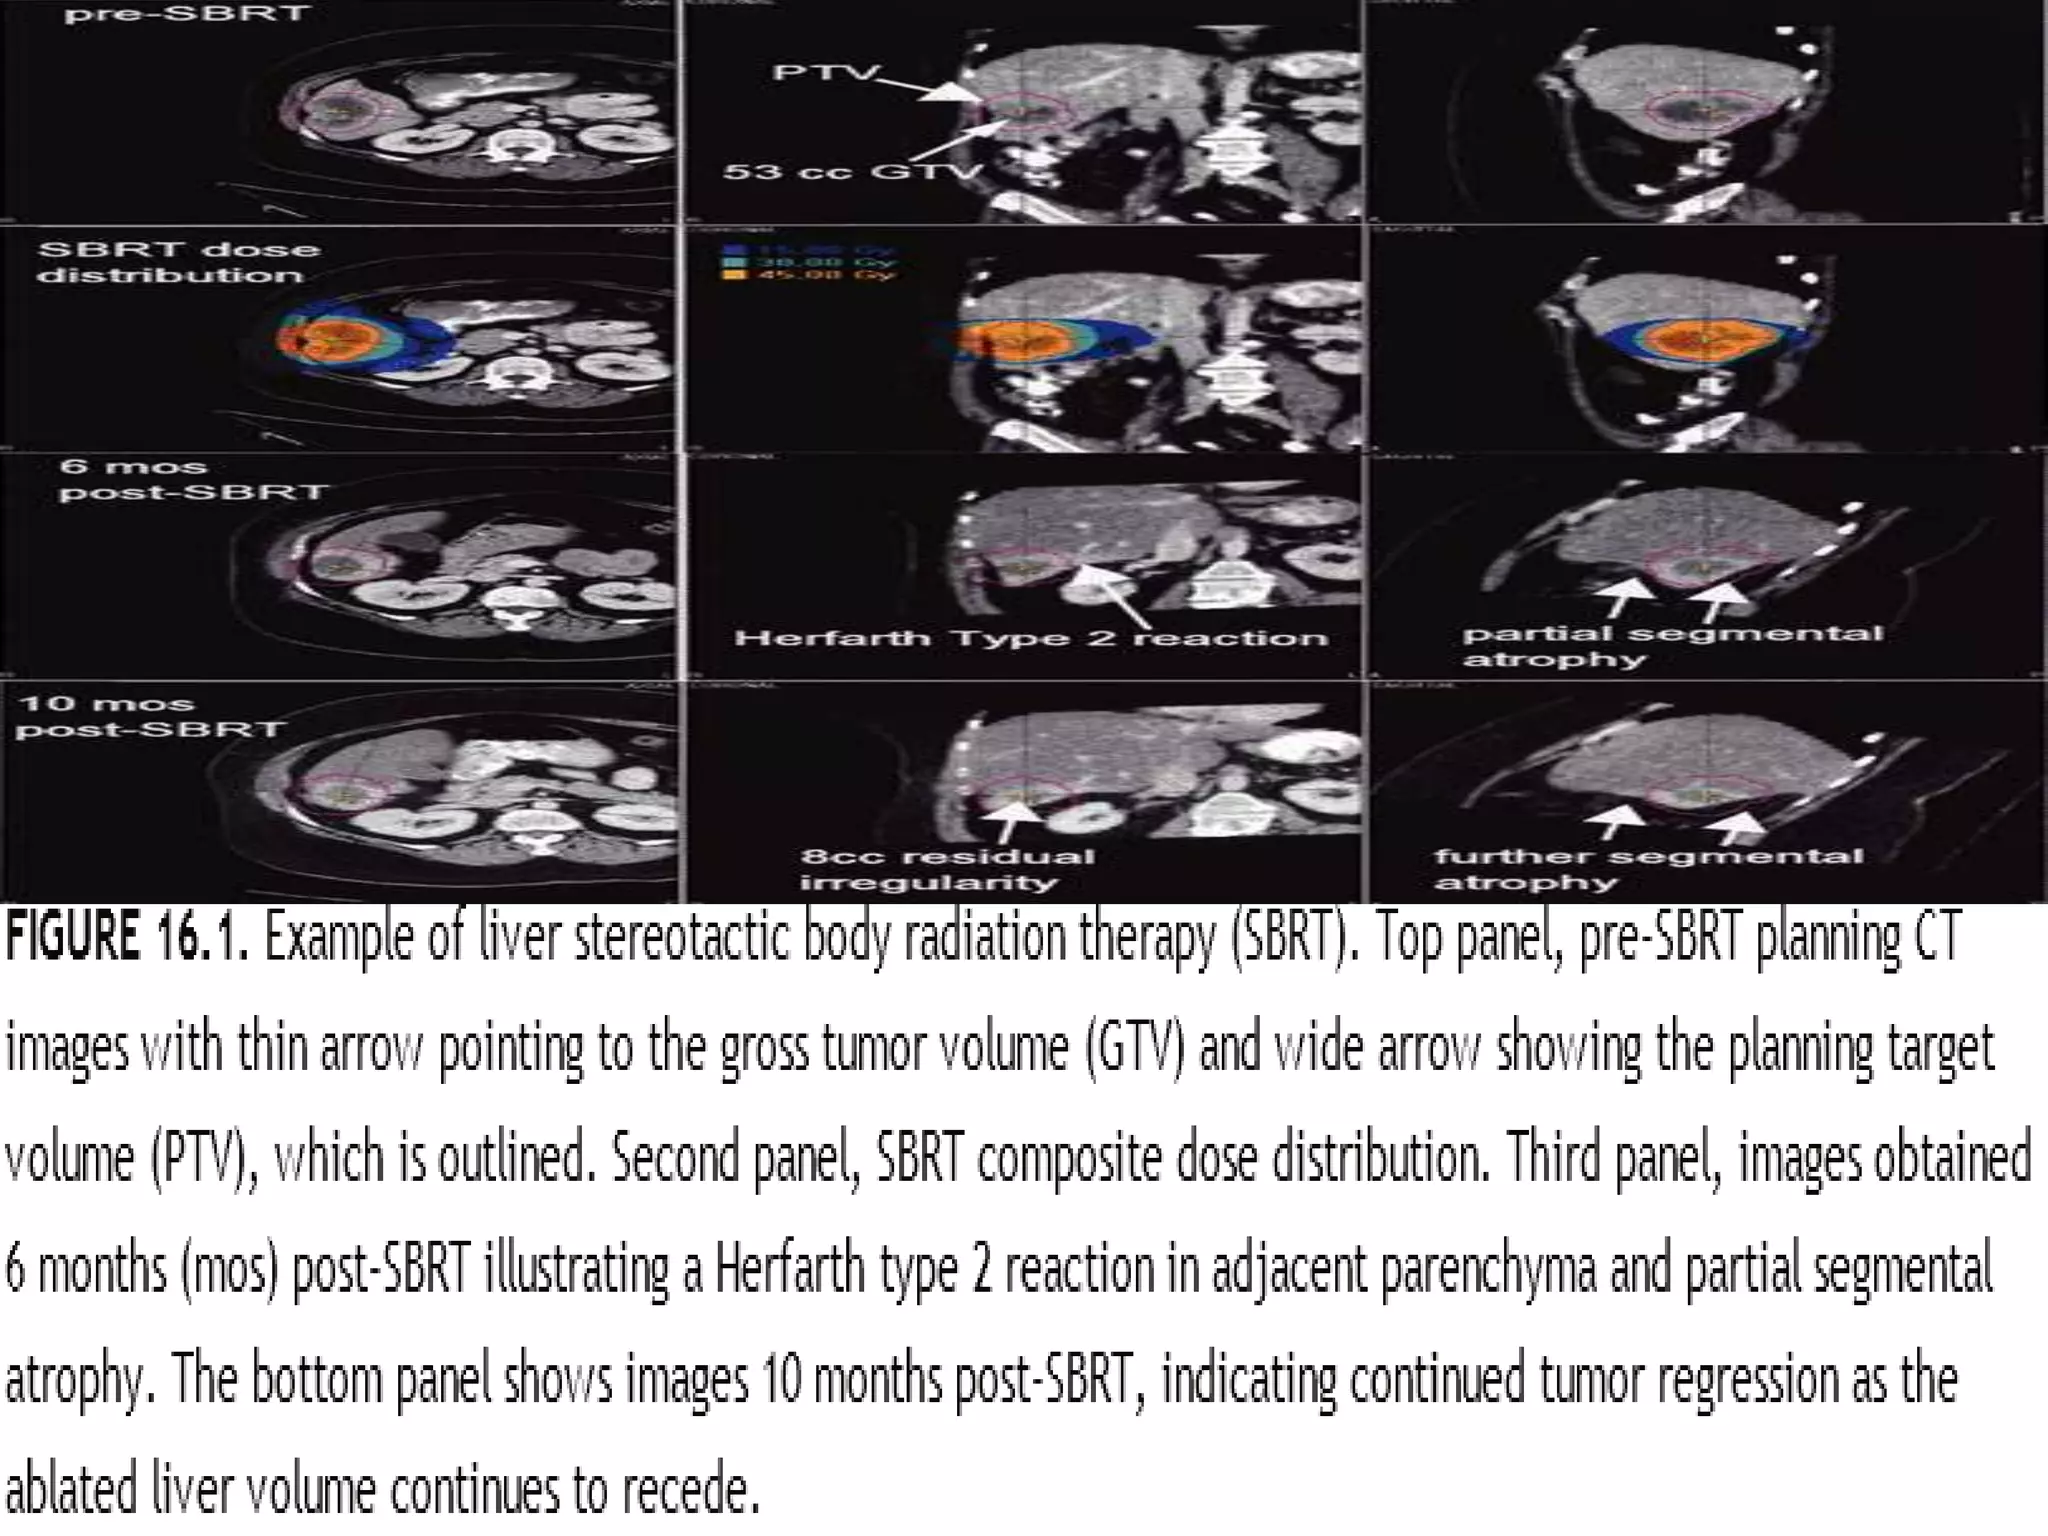

Several institutions have studied stereotactic body radiation therapy (SBRT) for primary lung cancer. Indiana University studies showed a maximum tolerated dose of 66 Gy for T2 lesions delivered over 3 fractions, with 1-year local control rates of 98%. Other studies from Aarhus University, Kyoto University, Air Force General Hospital in Beijing, and University of Marburg demonstrated 1-2 year local control rates ranging from 85-95% using SBRT dose fractions between 30-60 Gy delivered over 1 to 10 fractions.